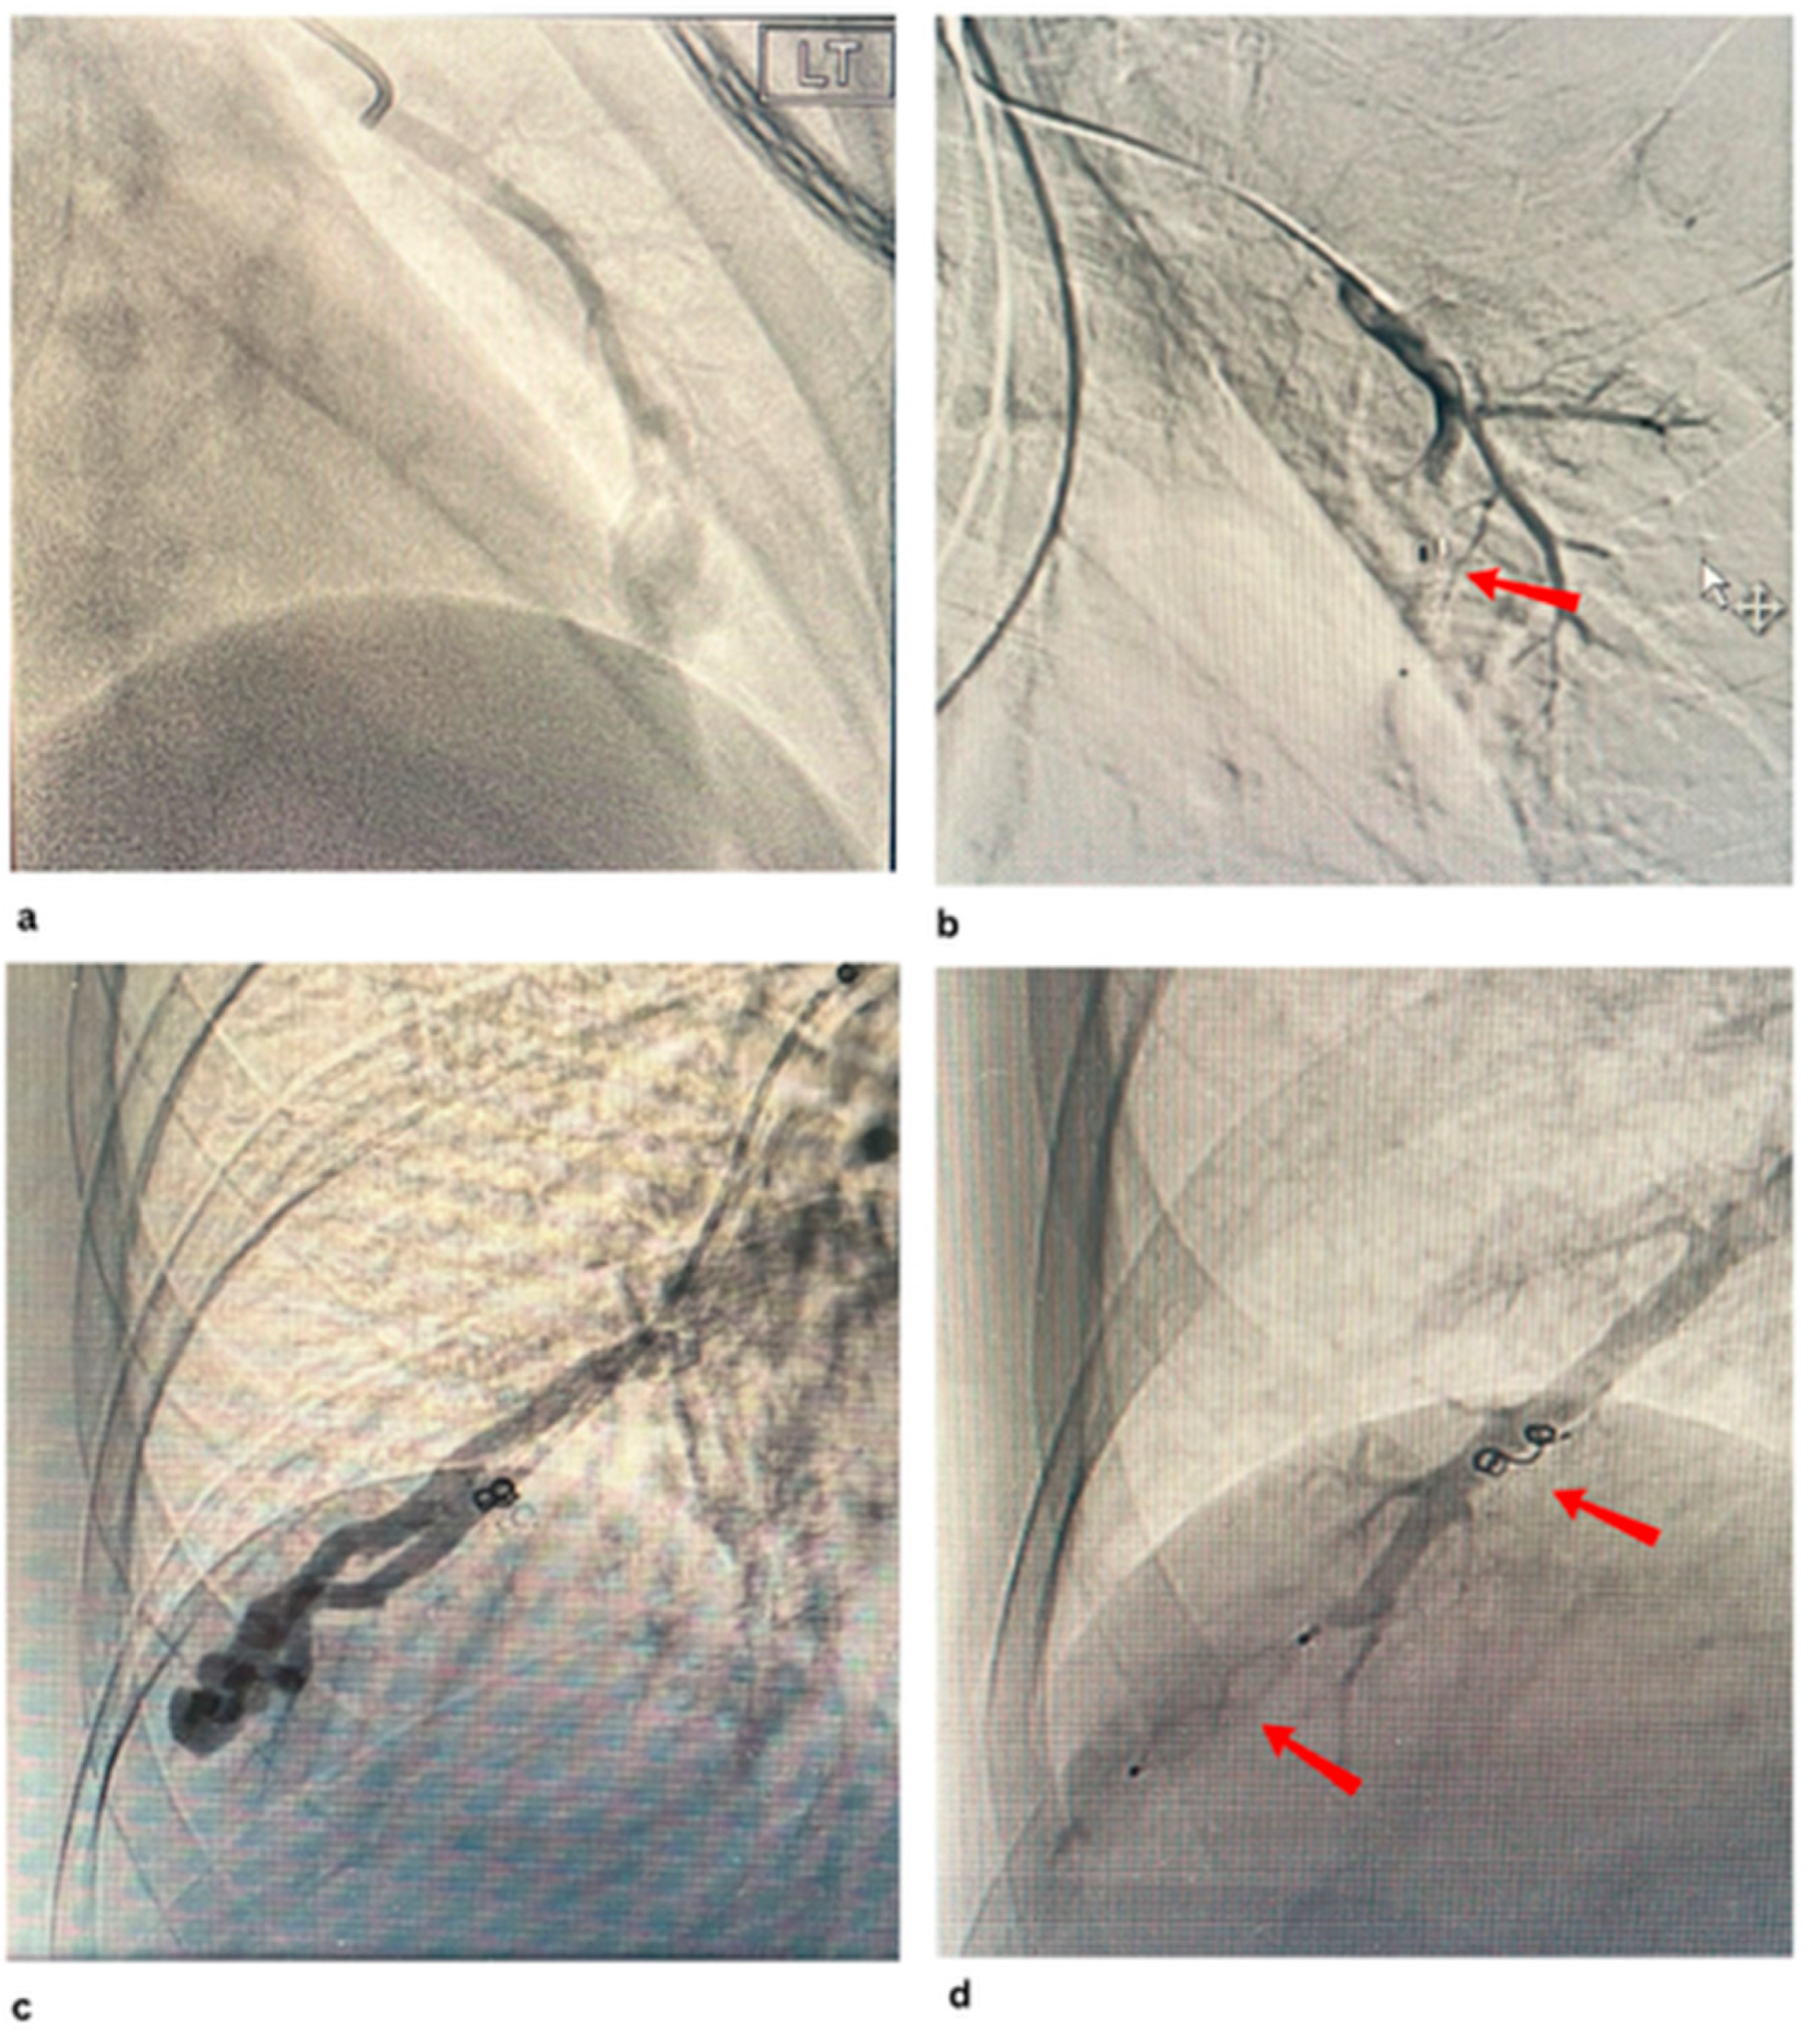

- Prasad, S.N.; Sharma, S.; Singh, V.; Phadke, R.V. Endovascular management of pulmonary arteriovenous malformations presenting as multiple brain abscesses. BMJ Case Rep. 2022, 15, e251593. [Google Scholar] [CrossRef] [PubMed]

- Greben, C.R.; Setton, A.; Putterman, D.; Caplin, D.; Lenner, R.; Gandras, E.J. Pulmonary Arteriovenous Malformation Embolization: How We Do It. Tech. Vasc. Interv. Radiol. 2013, 16, 39–44. [Google Scholar] [CrossRef]